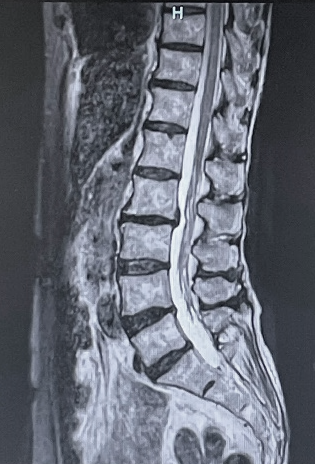

既に定評のある、脳神経、骨関節領域の他に、MRアンギオ(脳血管・四肢血管が描出可能)、MRCP(造影剤を用いない胆管・膵管画像)、急性期脳梗塞の診断(拡散強調像、MRアンギオや灌流画像を組み合わせることで治療方針の決定に有用)などの撮像法にも対応可能です。